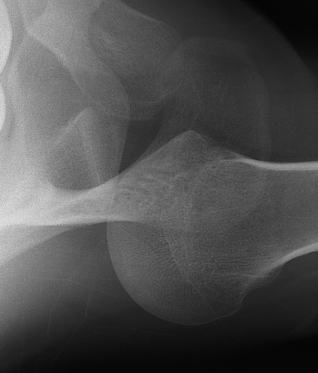

AP Xray

Abnormal overlap of humeral head on glenoid

Light-bulb sign - globular head secondary to internal rotation of the humeral head

Vacant Glenoid Cavity - > 6 mm space between humeral head and anterior rim of glenoid

Axillary Xray

Diagnostic - humeral head posterior to glenoid with evidence of reverse Hill Sachs